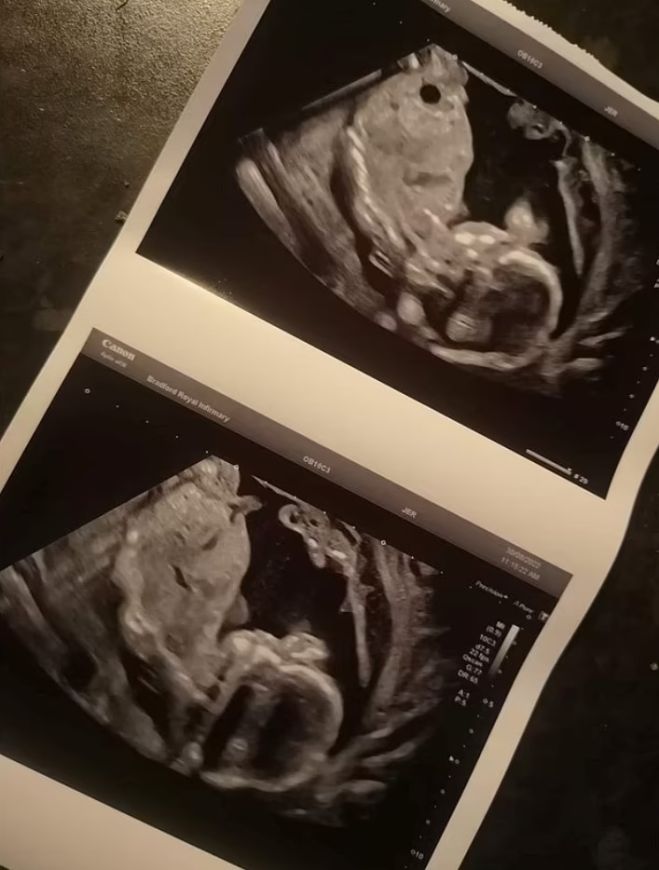

在英国有一位27岁的新手妈妈,汉娜,在怀孕20周时提早破水,紧急送院安胎。结果第二天,医生告诉她,已经检测不到宝宝的心跳,需要尽快安排引产。安娜接收不到,她凭着直觉,坚信自己的孩子还活着,要求医生再检查一次!

奇迹竟然发生了!再次进行检查的医生发现了宝宝的心跳。宝宝奥克利最终在第24周出生,但是过轻体重只有780g,需要待在保温箱里至少到明年2023年的2月9日。

除此之外,宝宝一出生就被诊断出坏死性小肠结肠炎,在出生后第8天就接受手术,并预计明年还会再进行更进一步的手术。汉娜透露,过去孩子需要依赖呼吸器,现在则不需要,情况可以说是乐观的,同时也希望可以早日带他回家。 .jpg?itok=tdRxiAsE)